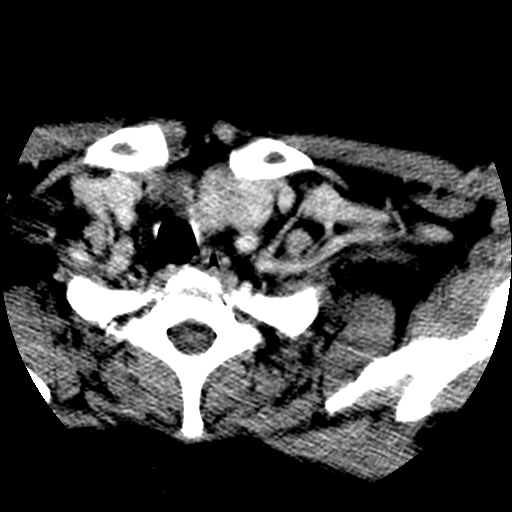

标题: CT25491:女,55岁,发现左侧甲状腺肿块一个月。 [打印本页]

标题: CT25491:女,55岁,发现左侧甲状腺肿块一个月。

女,55岁,发现左侧甲状腺肿块一个月,彩超示:甲状腺多发结节伴左叶结节液化。

考虑右叶结节性甲状腺肿,伴左叶钙化。主要(1)密度均匀,边境清。(2)病灶与血管界限清。

边界清,无明显强化,考虑考虑甲状腺腺瘤